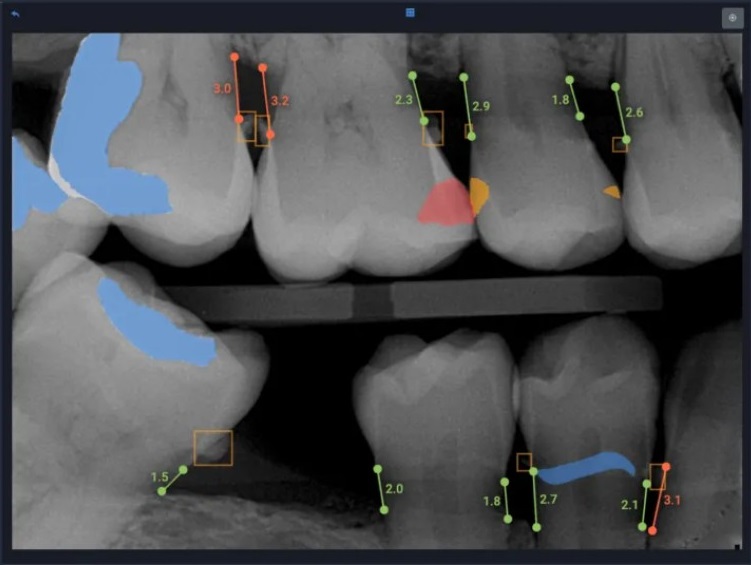

AI can be trained to analyse dental X-rays (OPGs and periapical images) using Convolutional Neural Networks (CNNs) and detect disease markers like bone loss and periodontal pockets. Training AI in reading CBCT scans may help detect bone resorption, attachment loss, and furcation involvement, often surpassing manual analysis. Such precise radiographic outcomes are changing the future of AI in dentistry.